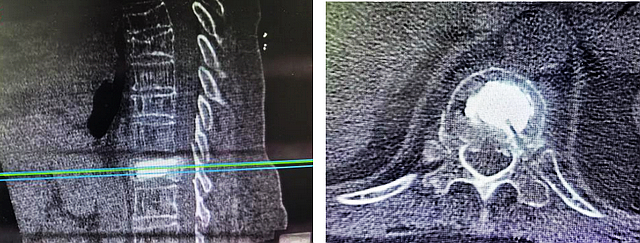

完善MRI、CT检查,明确为胸椎骨质疏松性椎体压缩性骨折,接诊的脊柱·肿瘤一组赵檬医生建议手术治疗。

经皮椎体后凸成形术是一项脊柱微创技术,是指在影像介导下经皮向骨折或破坏的椎体内注入骨水泥以达到增强骨折椎体的稳定性。这项技术可以明显缓解伤椎引发的疼痛,并增强椎体强度和稳定性,恢复椎体高度,防止伤椎持续塌陷,且手术麻醉风险低、手术时间短、手术创伤小、患者恢复快等优点。